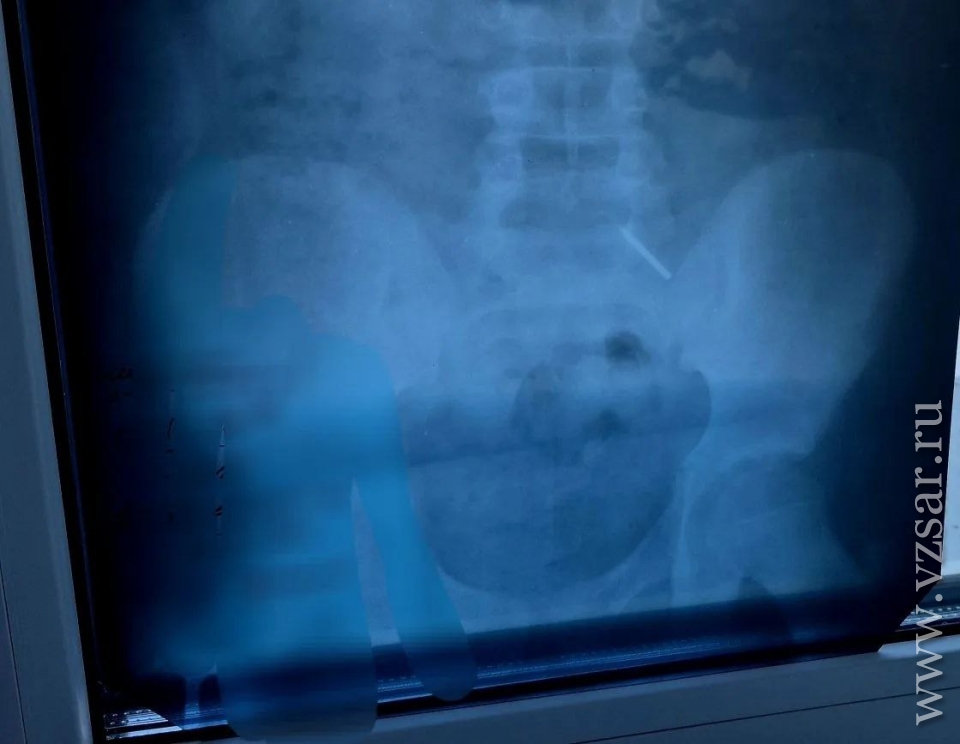

В Балаковской городской клинической больнице (Саратовская область) врачи спасли ребенка, проглотившего инородный предмет, сообщает тг-канал медучреждения.

В клинику поступил 11-летний школьник, который, как оказалось, проглотил часть циркуля.

"Эндоскопически достать предмет не представлялось возможным из-за позднего обращения пациента. Главной задачей было не допустить перфорации кишечника и кровотечения - мальчик находился под наблюдением врачей и рентгенологов. В итоге инородное тело вышло естественным путем. Пациент выписан домой", - рассказали в больнице.